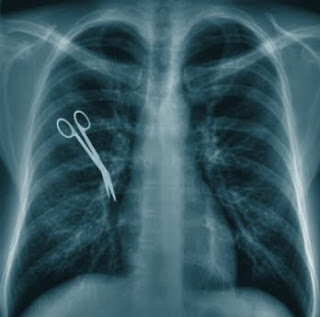

• Surgical malpractice – When surgical errors are made during a surgical procedure, all the people involved are liable for surgical malpractice. Doctors, nurses, anesthesiologists, and others in the operating room are obliged to carry out a certain duty of care, but the failure to do so can result in brain damage or other serious injuries for the patient.